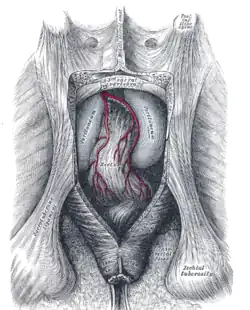

Muscles of the female perineum. (Urogenital triangle is roughly equal to top half of diagram.) | |

Muscles of male perineum. (Urogenital triangle is roughly equal to top half of diagram.) | |